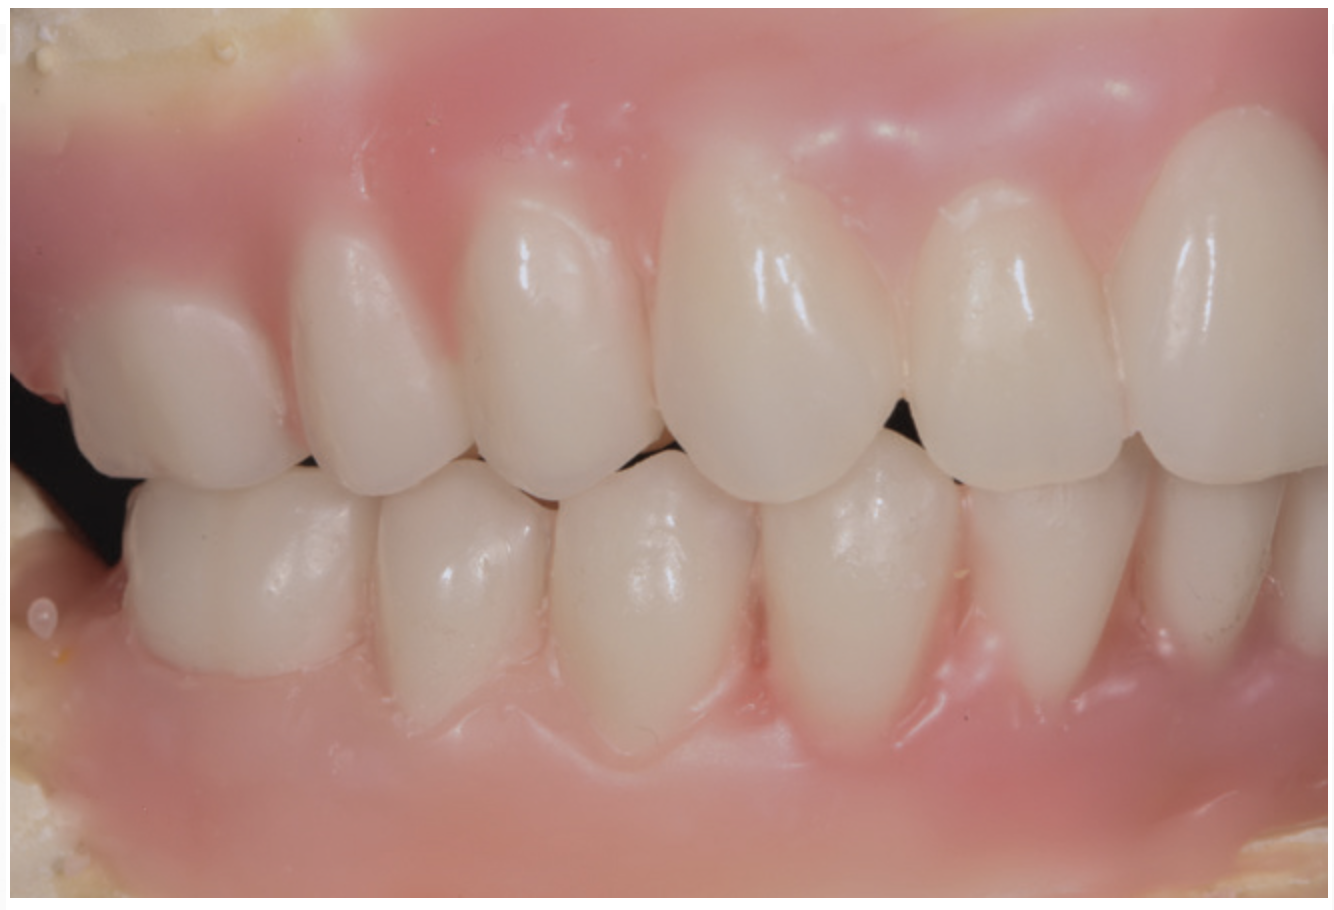

Fig 2. Potential “All-on-4” patient with terminal dentition who was unhappy with his smile esthetics.

Figure 2